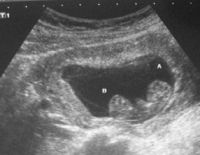

Siêu âm thai 4 tuần tuổi có quan trọng và cần thiết không?

Siêu âm thai 4 tuần tuổi là siêu âm trong giai đoạn đầu của thai kỳ. Ở tuần tuổi này, thai nhi còn rất rất nhỏ. Nên nhiều mẹ thắc mắc liệu siêu âm thai 4 tuần tuổi có cần thiết không và có quan...